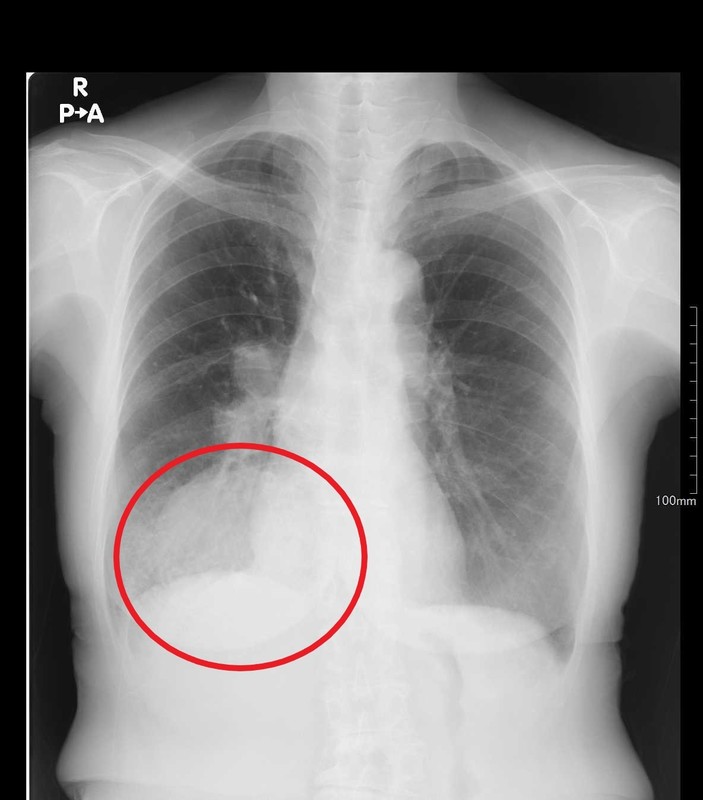

③胸水貯留

肺を包んでいる空間である胸腔に様々な原因で水がたまってしまっている状態です。

炎症が強い場合には胸痛の症状が出たり、呼吸困難や呼吸不全などの症状を認めたりします。

胸水が貯留する原因は数多くあり、感染症によって膿(うみ)がたまる膿胸や悪性腫瘍(肺癌や胸膜中皮腫など)による癌性胸水、心不全による循環不全、肝硬変、栄養障害など実に様々です。

症状や経過、血液検査の結果に加えて胸水を抜き取って検査(細菌検査や胸水の性質を調べる)を行い総合的に原因を探ります。原因に応じて抗生物質を投与したり、心臓や肝臓の治療をしたり栄養状態改善をはかったりします。

胸水が大量にたまっている場合には、気胸のときと同様に針やチューブでたまった水を抜き出したりするドレナージを行うこともあります。

↑それぞれ肺癌を疑う陰影(赤丸部分)を認めます。